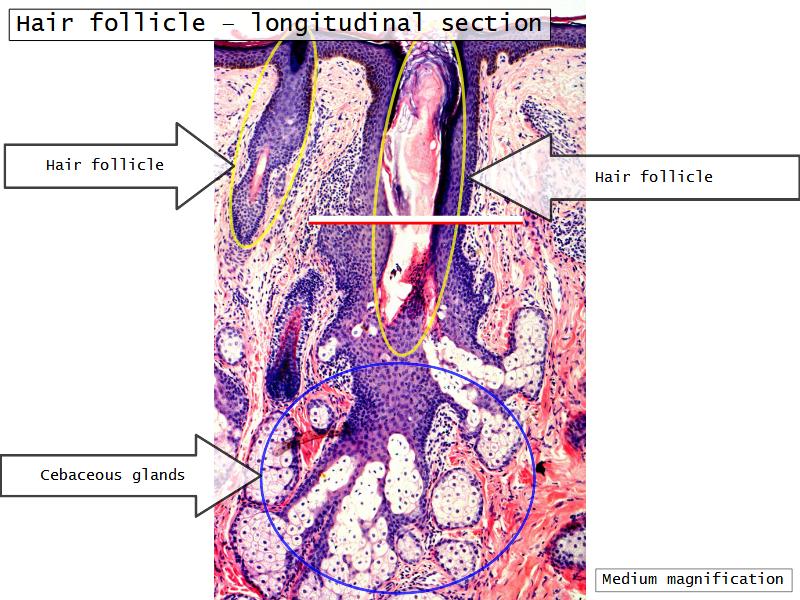

Slides: Respiratory System

- Slide 71: Nostril

Nostril